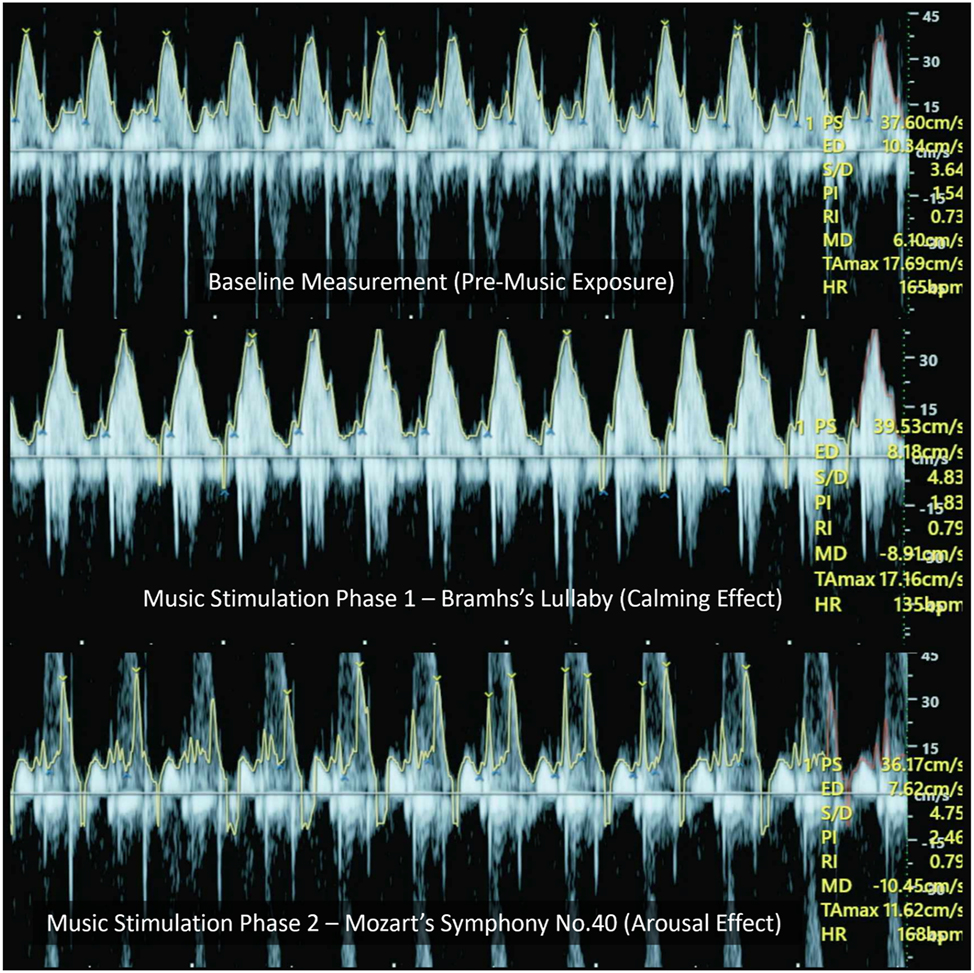

The mean fetal heart rate (FHR) demonstrated clear variations across conditions, reflecting distinct physiological responses to auditory stimulation. Table 1 summarizes fetal heart rate and Doppler values across all conditions. Baseline FHR was recorded at 141.3 ± 16.0 bpm. During exposure to Brahms’ Lullaby, FHR significantly decreased to 133.1 ± 14.6 bpm, indicating a calming effect, while exposure to Mozart’s Symphony No. 40 led to a significant increase in FHR to 149.8 ± 15.3 bpm, suggesting an arousing response. These observations support the hypothesis of stimulus-specific cardiovascular reactivity in the fetus. Parallel changes were observed in Doppler parameters, including peak systolic velocity (PS), end-diastolic velocity (ED), and time-averaged maximum velocity (TAMax), which followed a similar trend of modulation, further indicating fetal autonomic adaptability to musical tempo. Representative Doppler waveforms illustrating these changes under baseline, Brahms, and Mozart conditions are shown in Figure 2.

This Figure presents representative trans-mitral/tricuspid Doppler waveforms recorded under three auditory conditions. Although aliasing artifacts are visible, especially at peak velocities, the E-wave peak velocities (representing early diastolic filling) and time-averaged maximum velocities (TAMax, reflecting average flow envelope) were assessed within each condition. The changes observed across Brahms’ and Mozart’s stimuli reflect alterations in diastolic inflow dynamics, which are consistent with autonomic modulation.

Color Doppler M-mode imaging of fetal cardiac responses to music stimulation (qualitative visualization only). This Figure presents qualitative M-mode Doppler visualizations of fetal cardiac activity across three auditory conditions: (Top) baseline (pre-music), (middle) Brahms’ Lullaby (calming music), and (Bottom) Mozart’s Symphony no. 40 (stimulating music). These color Doppler M-mode images do not provide precise velocity measurements but are used here to illustrate changes in fetal heart rate (FHR) and Doppler flow intensity. Compared to baseline (∼140 bpm), exposure to Brahms’ Lullaby shows a visible reduction in heart rate (∼133 bpm) and softened Doppler signal intensity, reflecting parasympathetic activation. In contrast, the Mozart condition shows a marked increase in FHR (∼150 bpm) with intensified flow signals, suggestive of sympathetic arousal. These visualizations highlight the temporal and qualitative changes in fetal cardiac function in response to musical stimuli and support the neuromodulatory potential of prenatal auditory therapy.

This alignment between cardiac modulation and behavioral state regulation highlights the functional integration of the fetal ANS and central nervous system. Figure 8 further illustrates these tempo-dependent changes in fetal heart rate and Doppler flow intensity using color Doppler M-mode images. Fast-tempo music may activate cortical-subcortical pathways – such as the limbic system and hypothalamic-pituitary-adrenal (HPA) axis – inducing transient arousal responses, as previously demonstrated in studies using vibroacoustic stimulation and facial expression monitoring [3], 24]. Conversely, melodic, slow-tempo music likely enhances vagal tone through brainstem-mediated relaxation circuits, promoting cardiovascular deceleration and behavioral stabilization.